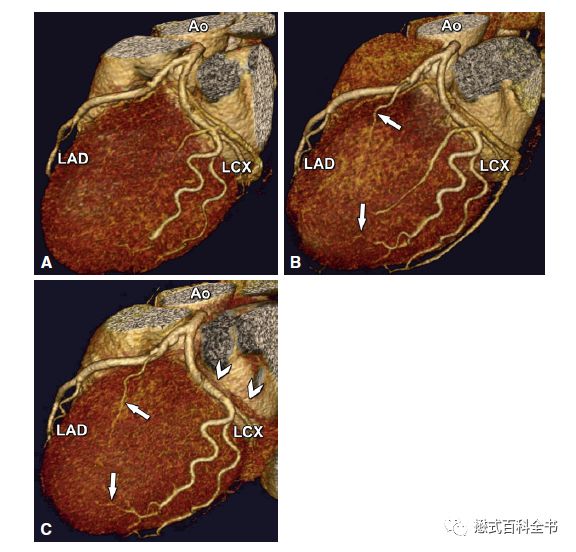

图13:心脏冠脉成像是目前CT的主要应用之一

图14:CT在心血管中的应用